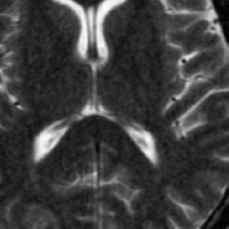

(d) Circle of Willis

Figure 2: Test Images.

We turn now to test TDIHT for high dimensional signals. We test the performance of several MRI images: the Shepp-Logan phantom, FLAIT brain image, T2 Sagittal view of the lumbar spine and the circle of Willis. The first image is of size 256×256256256256\times 256, while the other are of size 512×512512512512\times 512. They are all presented in Fig. 2.

We focus on the recovery of these images from a few number of Fourier measurements. With 𝛀𝛀{\mathbf{\Omega}} set to be the undecimated Haar transform with one level of resolution (redundancy four) and 𝐃𝐃\mathbf{D} its inverse transform, we succeed to recover the phantom image using only 181818 sampled radial lines, which is only 6.5%percent6.56.5\% of the measurements. This number is only slightly larger than the number needed for GAP, relaxed ASP (RASP) and Relaxed ACoSaMP (RACoSaMP) in [10, 38]. The advantage of TDIHT over these methods is its low complexity as it requires applying only 𝐌𝐌{\mathbf{M}} and its conjugate and 𝛀𝛀{\mathbf{\Omega}} and its inverse transform while in the other algorithms a high dimensional least squares minimization problem should be solved. Note also that for AIHT and RAHTP the number of radial lines needed for recovery is 353535 and for IHT (with the decimated Haar operator with one level of resolution) we need more than 505050 radial lines.